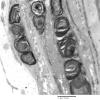

1B3 Diabetic NP (Case 1) Plastic 60X

1B5 Diabetes, DLRPN (Case 1) NF 40X 3

1B6 Diabetes, DLRPN (Case 1) NF 40X 1